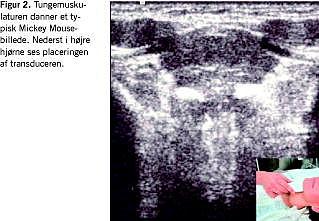

Man starter skanningsproceduren med B-mode- eller gråskala-ultralyd. Man skal sikre sig, at transduceren vender rigtigt. Dernæst starter man på venstre side af halsen i region IV/nedre jugulære. Her kan man typisk se glandula thyroidea, arteria carotis og vena jugularis interna, musculus sternocleidomastoideus, og hvis man beder patienten om at synke, kan øsofagus identificeres i dybden. Man følger de store kar i kraniel retning til region III/midterste jugulære, hvor øvre thyroideapol og strubelåget kan ses, når patienten synker. På overgangen mellem region III og region II/øvre jugulære ses tungebenet medialt, og længere kranielt ses carotisbifurkaturen, hvor der hyppigt ses en lymfeknude/angulærknuden, som typisk måler 1 × 1,5 cm hos raske. Øverst ses glandula parotis, som bør skannes i hele dens udstrækning, da der tit ses forstørrede lymfeknuder i parotissubstansen ved maligne sygdomme i ansigtet. Herefter kan man med fordel fortsætte ned foran musculus trapezius i region V/posteriore trekant langs accesoriuskæden. Dernæst skannes fra region II frem mod region I/submandibulært og submentalt, hvor man kan identificere glandula submandibularis og sublingualis. Her ses ofte forstørrede lymfeknuder hos patienter med relevant sygdom i hovedhalsområdet. Transduceren bør også føres ind under hagen, hvor tungemuskulaturen danner et typisk billede, der ligner Mickey Mouse, Figur 2 . Proceduren foretages på samme vis på højre side. Der bør altid skannes på begge sider af halsen, uanset om der i de fleste tilfælde er tale om unilateral sygdom.